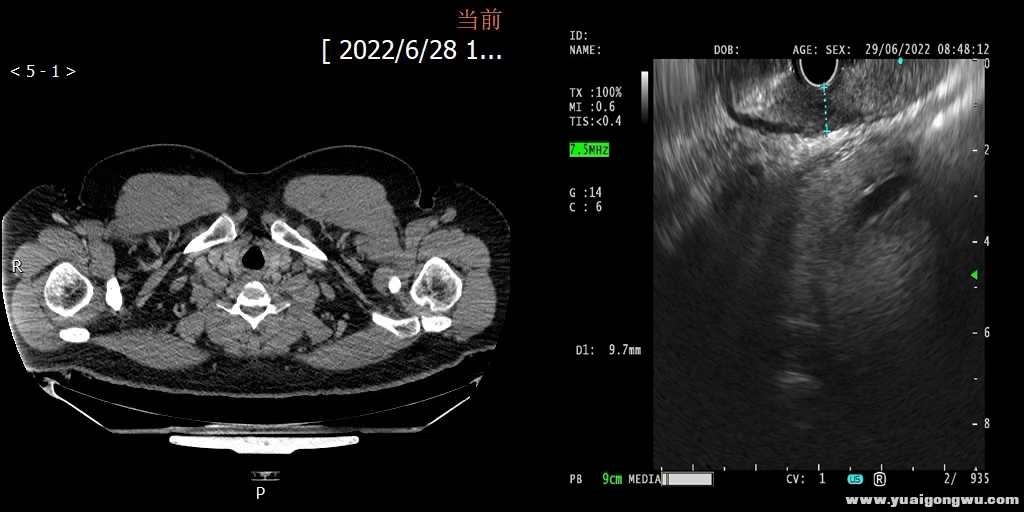

经过进一步的CT、胃镜活检病理和超声检查,吴寒最终确诊为食管下端低分化腺癌(cT3N0M0 III期)。医肿深圳胸外科主导的MDT(多学科诊疗)团队经过初步讨论,认为针对他的病情,根据目前国内外研究证据和指南推荐,先进行术前新辅助治疗能争取到最大的生存获益可能,是最佳的治疗决策。听到 “暂时不手术”的决定,吴寒没有惊惶,而是镇定地配合医生的治疗建议。

吴寒经过CT、胃镜等全面检查后,确诊食管下端低分化腺癌 cT3N0M0 III期